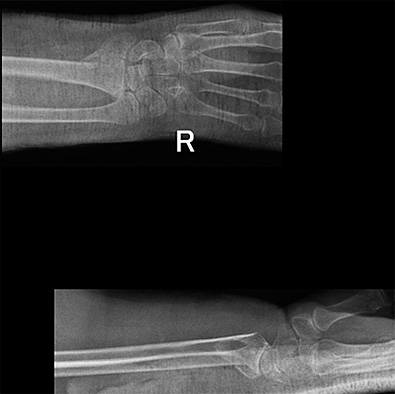

Пациент К. 45 лет. Травма в результате ДТП. При поступлении в клинику диагностирован открытый многооскольчатые переломы дистальных метаэпифизов локтевой и лучевой кости.

При поступлении выполнена экстренная операция – фиксация перелома в аппарате внешней фиксации.